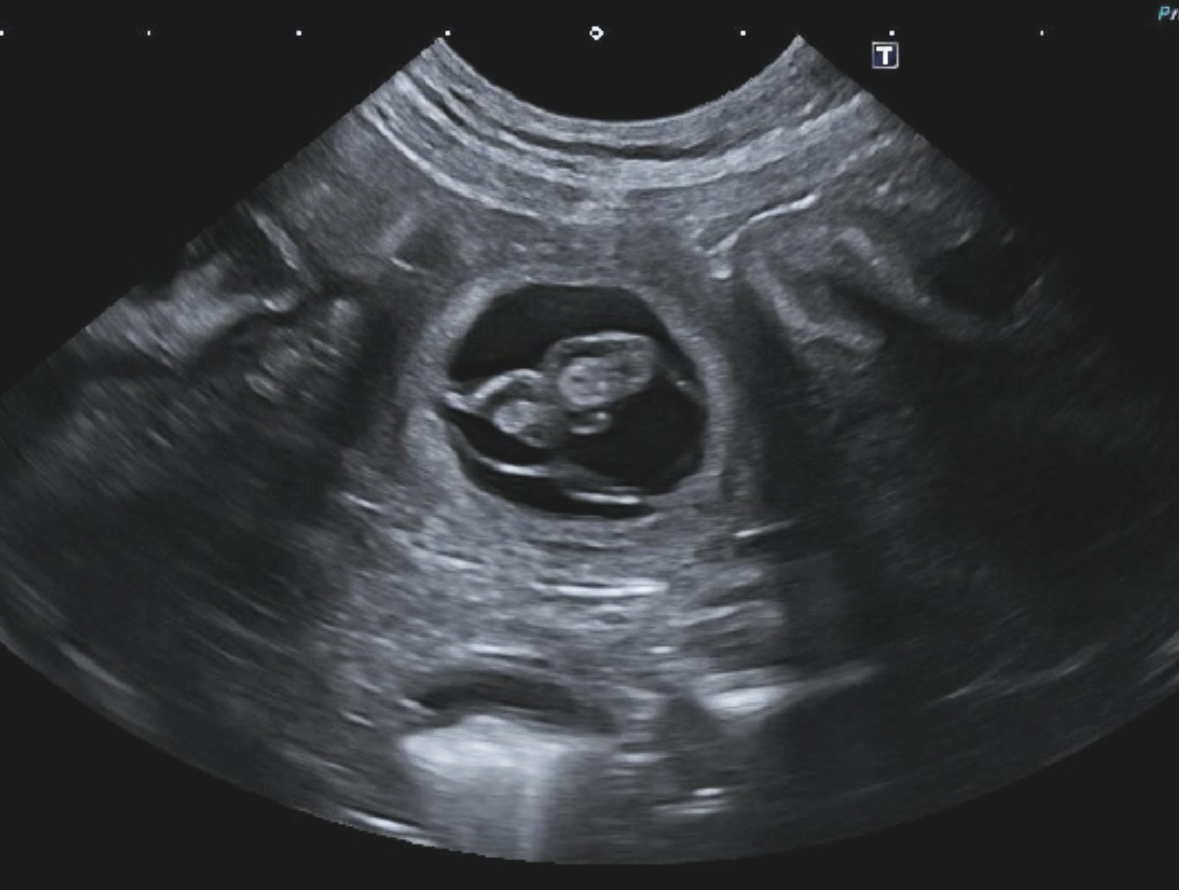

Březost potvrzena

S radostí můžeme oznámit, že krytí na konci srpna bylo úspěšné a na konci října se můžeme těšit na štěňátka. Přijímáme rezervace.

Na ultrazvuku všem „štěňátkům“ krásně ťukala srdíčka. Doufáme, že i nadále bude vše probíhat bez komplikací.